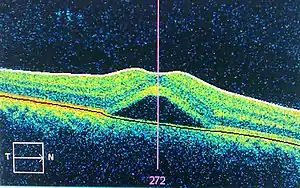

Figure 22. Typical optical setup of single point OCT |

Figure 23. Central serous retinopathy,imaged using optical coherence tomography |

Optical coherence tomography (OCT) is a medical imaging technique using low-coherence interferometry to provide tomographic visualization of internal tissue microstructures. As seen in Fig. 22, the core of a typical OCT system is a Michelson interferometer. One interferometer arm is focused onto the tissue sample and scans the sample in an X-Y longitudinal raster pattern. The other interferometer arm is bounced off a reference mirror. Reflected light from the tissue sample is combined with reflected light from the reference. Because of the low coherence of the light source, interferometric signal is observed only over a limited depth of sample. X-Y scanning therefore records one thin optical slice of the sample at a time. By performing multiple scans, moving the reference mirror between each scan, an entire three-dimensional image of the tissue can be reconstructed.[101][102] Recent advances have striven to combine the nanometer phase retrieval of coherent interferometry with the ranging capability of low-coherence interferometry.[74]